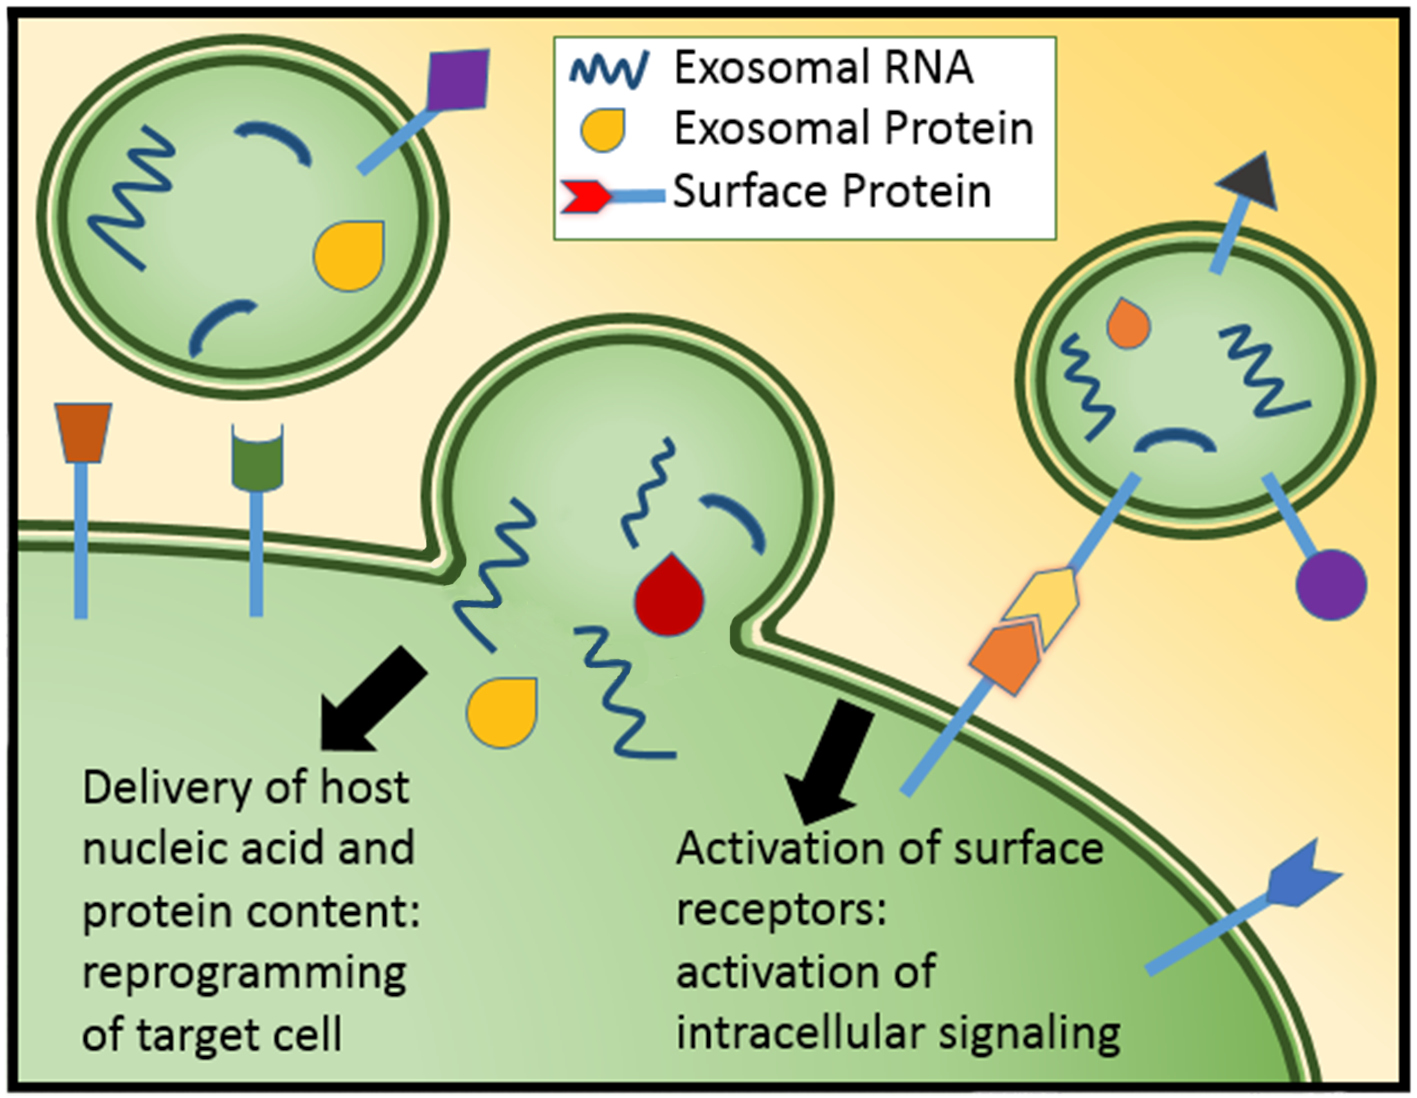

The untapped potential of urine shed bladder cancer exosomes: biomarkers, signaling, and therapeutics

Abstract 197 | HTML Downloads 60 PDF Downloads 54 | DOI https://doi.org/10.14440/bladder.2014.38Page e7